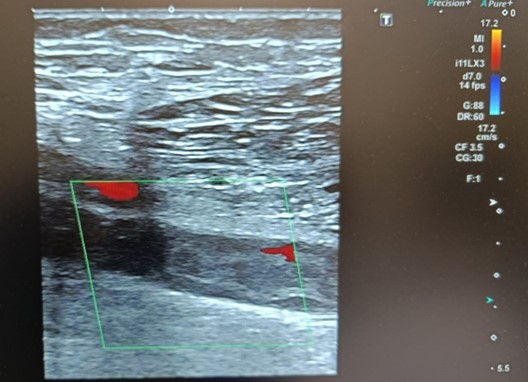

Ecografía Doppler

Ausencia de compresibilidad y material ecogénico compatible con trombosis en cayado de safena interna y externa, vena femoral superficial distal , vena poplítea y venas gemelares. Troncos tibioperoneos permeables.